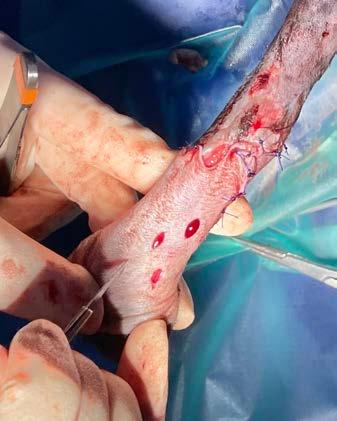

La epiglotopexia incisional se realiza escindiendo una cuña de 10 mm de ancho por 5 mm de largo de la mucosa de la epiglotis, en su aspecto lingual

(Fig. 3A), y una escisión similar en la base de la lengua. Este defecto se sutura a la base de la lengua mediante un patrón de 1-4 puntos de colchonero vertical independientes o puntos simples, pudiendo incluir el cartílago epiglótico (Figs. 3B y 3C), con la tensión suficiente para que la epiglotis permanezca horizontal (Fig. 3D). Con ello se espera la creación de una escara fibrótica en la base de la epiglotis que pueda mantenerla en su sitio y limitar su desplazamiento caudal hacia la rima glottidis 1,2,11

Figura 3. Secuencia de la realización de la técnica de epliglotopexia incisional. (A) Detalle de la realización de la incisión en el aspecto lingual de la epiglotis. (B) Detalle de las estructuras anatómicas sobre las que se lleva a cabo la técnica quirúrgica. A: epiglotis; B: base de la lengua. (C) Detalle de las suturas de la epiglotis a la base de la lengua incluyendo al cartílago epiglótico (A-B) y epiglotis (*). (D) Detalle final del posicionamiento horizontal de la epiglotis respecto a la lengua mediante sutura por puntos simples incluyendo al cartílago epiglótico.